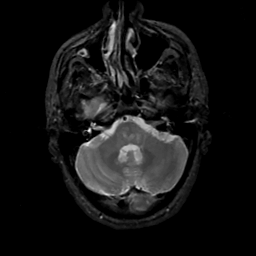

MR Study #14, June 2, 1991 -- Slice #11

[Home][Help][Clinical][Tour 1][Tour 2] Slice 11